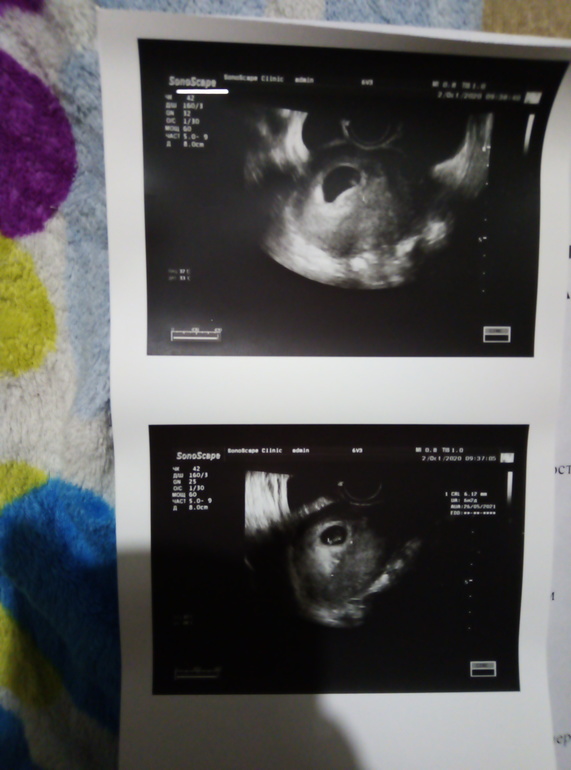

УЗИ 7 недель результаты

Была 17.10 на УЗИ, по М написали 7+1 (по факту думаю 6+6 или 7, так как О отслеживала по БТ, была на 16 дц, что для меня даже рано)

Узист сказала, что соответствуем сроку

КТР 9 мм, СВД ПЯ 20 мм, чсс 136 уд/мин

Начала переживать, не маловато ли ПЯ